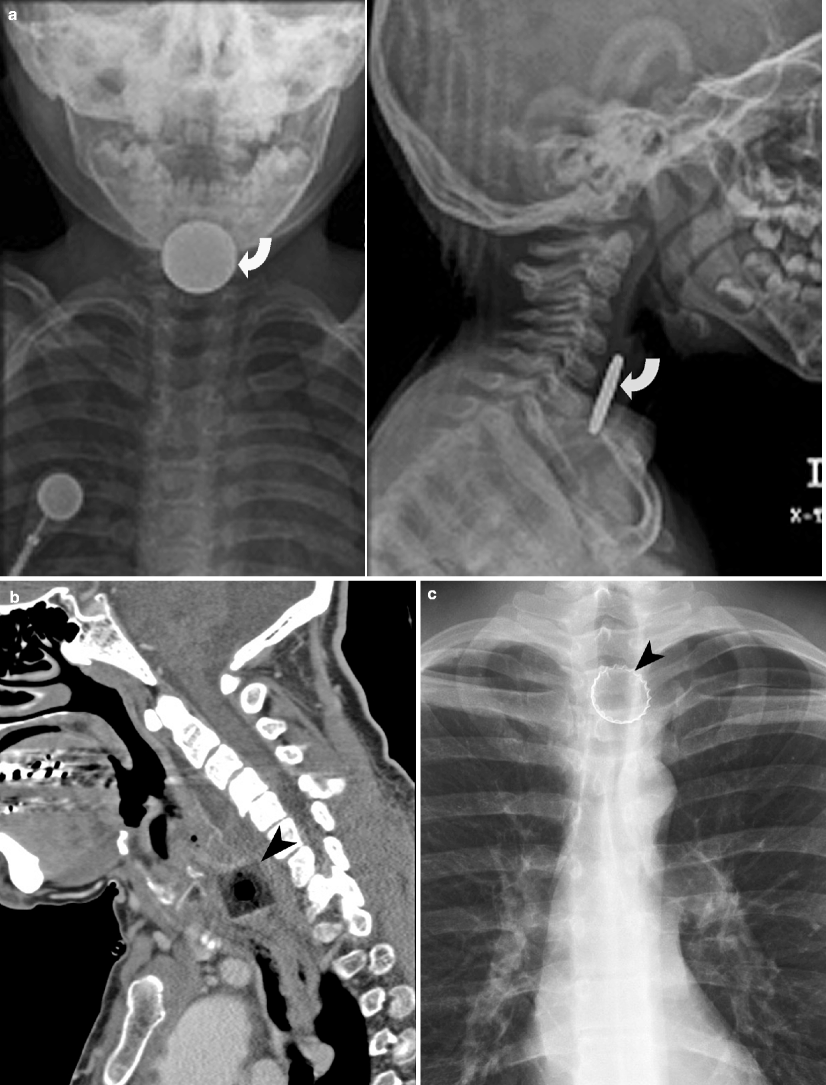

From radiologykey.com

Imaging of Neck Emergencies Radiology Key Criteria For Neck X Ray The presence of a neck mass or lymphadenopathy should be guided by the acr appropriateness criteria ® topic on “neck mass/adenopathy”. This web page provides guidelines for imaging modalities for different variants of cervical neck pain or radiculopathy. Find out when ct without contrast may be. Radiographs are appropriate as initial imaging for cervical or neck pain in the absence. Criteria For Neck X Ray.